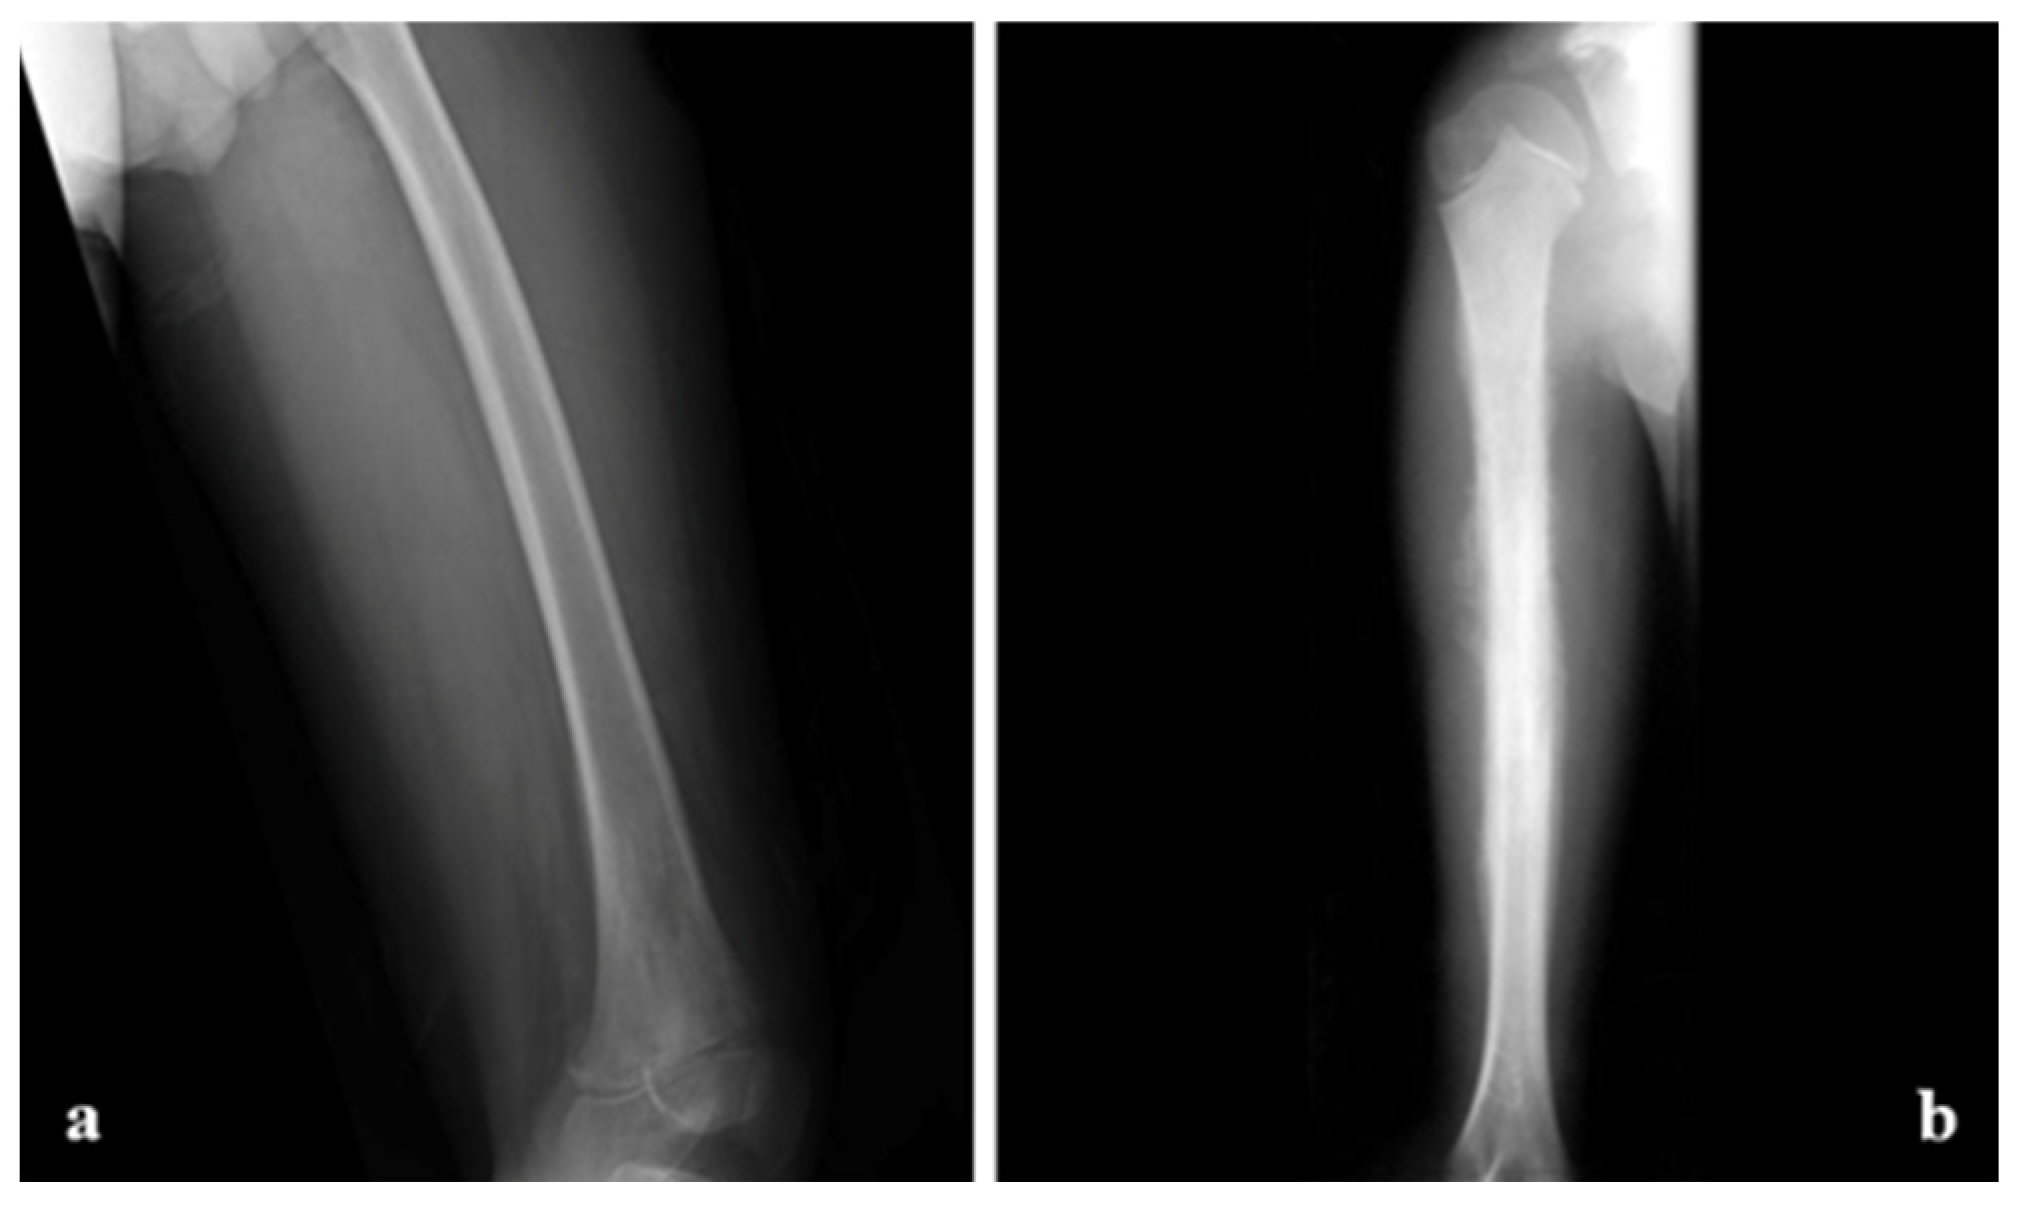

The first-level investigation is represented by the X-ray, in which the radiographic aspect is that of a malignant tumour that originates inside the bone, rapidly destroying the cortical, the nascent sol appearance, the periosteal lift with the formation of the Codman’s triangle, the apposition of new bone in the tissues (Figure 1a,b).

Figure 1. (a) Osteosarcoma. Radiographic examination shows eccentric erosive alteration interesting the medial contour of the femoral metaphysis, with presence of ill-defined tumefaction defined extrinsic to the adjacent soft parts. In the context of the bony lesion, a dual component is osteosclerotic and osteolytic (mixed form). It is associated with longitudinal periosteal reaction on the inner side (arrow curve) and with the classic appearance of triangular salience (“the Codman’s triangle”) on the outer slope (straight arrow). (b) A 12-year-old boy has osteosarcoma at the distal left femur, characterised by a broad zone of transition, osteoid matrix, and an active periosteal reaction (Codman triangle-arrows). Radiopaedia.org.